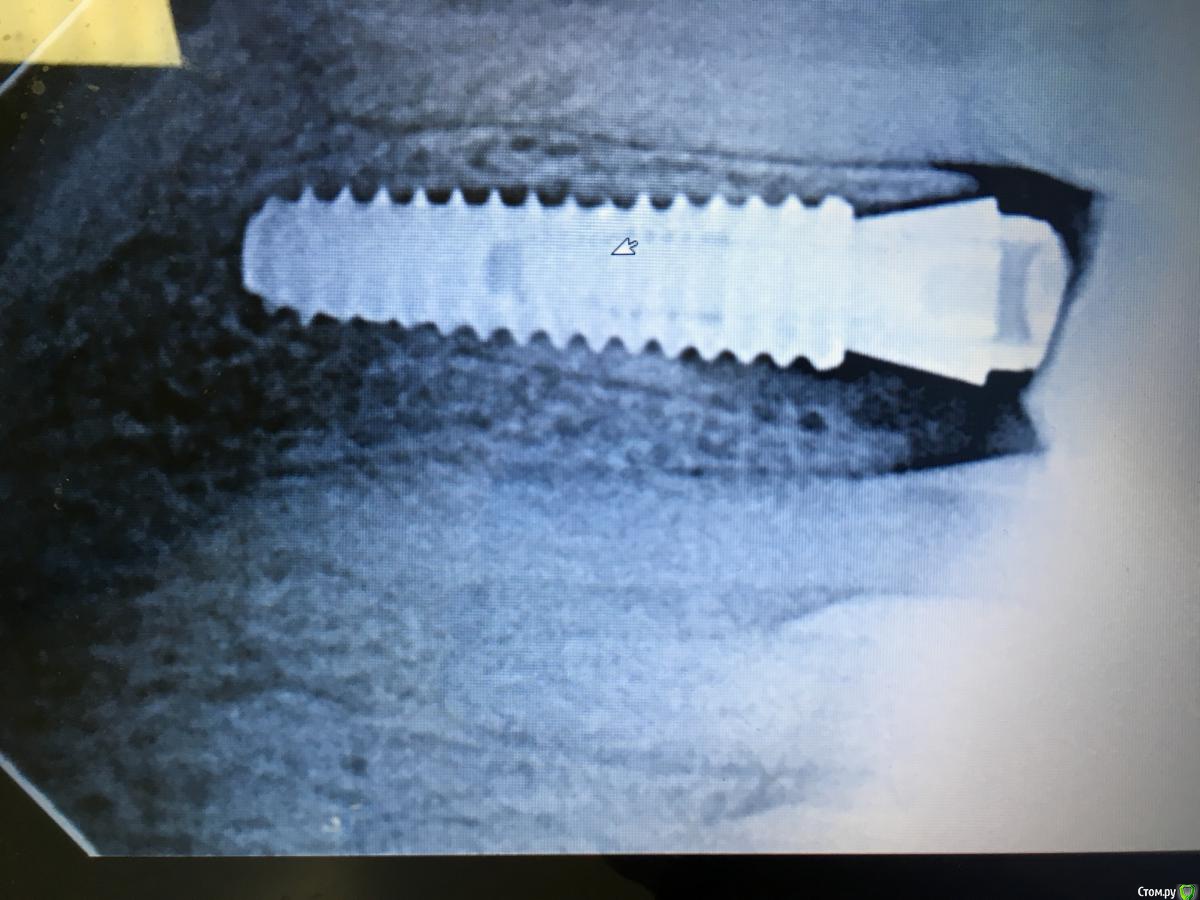

kamranchick Опубликовано 26 августа, 2018 Поделиться Опубликовано 26 августа, 2018 Какой прогноз коллеги? Ссылка на комментарий

kamranchick Опубликовано 27 августа, 2018 Автор Поделиться Опубликовано 27 августа, 2018 Задачи не было сделать щит))Щит от слова " оу щит мэн"После одномоментного удаления не увидел кусочек зуба который импрегнировался в лунке, поставил имплик и только потом увидел на рвг Ссылка на комментарий

Nazim_NV86 Опубликовано 26 августа, 2018 Поделиться Опубликовано 26 августа, 2018 "Щит" не должен касаться самого имплантата. В вашем случае это не "щит", а осколок зуба, который скорее всего приведёт к тому что написал Evikrol. Ссылка на комментарий

колесников Опубликовано 26 августа, 2018 Поделиться Опубликовано 26 августа, 2018 Качество щита лучше оценивать на кт в боковой проекции 1 Ссылка на комментарий